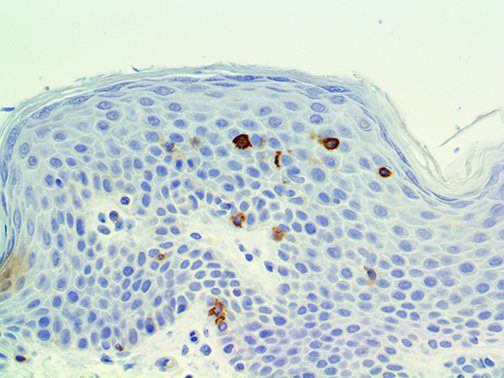

It is the ICU physician who is most likely to witness one of the deadliest manifestations of the abnormal immunological response, the cytokine storm syndrome (CSS). This response is also referred to by some as the cytokine release syndrome (CRS). CSS is characterized by continuous activation and expansion of macrophage and lymphocyte populations, which secrete large amounts of cytokines, causing the cytokine storm. This massive cytokine release is akin to hemophagocytic lymphohistiocytosis (HLH) disease, a syndrome characterized by initial unchecked and persistent activation of cytotoxic T lymphocytes and NK cells.